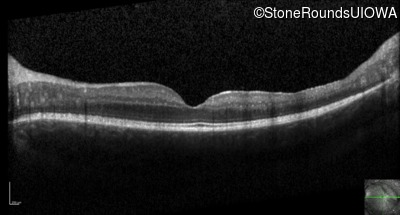

Optical Coherence Tomography - Left - 20/32

Exemplar / OCT Stack